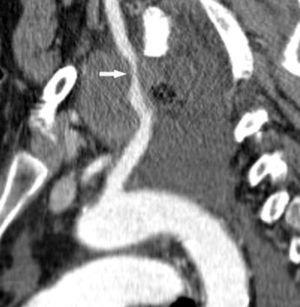

Una ventaja adicional de la TCMC es la capacidad de realizar, como parte del estudio de extensión, una angiografía TC (angioTC) en los tumores de localización central candidatos a cirugía y, fundamentalmente, en aquellos pacientes con hemoptisis que podrían ser subsidiarios de embolización terapéutica. El estudio vascular permite tener un excelente mapa para la cirugía, que ayuda enormemente al cirujano a la hora de planificar la intervención (fig 8). En los pacientes con hemoptisis amenazante, la demostración de una arteria sistémica hipertrófica sirve de guía para la arteriografía y subsecuente terapia endovascular (fig. 9).

Fig. 9.--Hemoptisis masiva secundaria a neoplasia de pulmón. (A) Corte axial con contraste que muestra el origen de la arteria bronquial derecha en la aorta descendente. (B) Reconstrucción de volumen en la que se pone de manifiesto la localización exacta de la arteria bronquial derecha hipertrófica y su exquisita correlación con la angiografía selectiva (C).